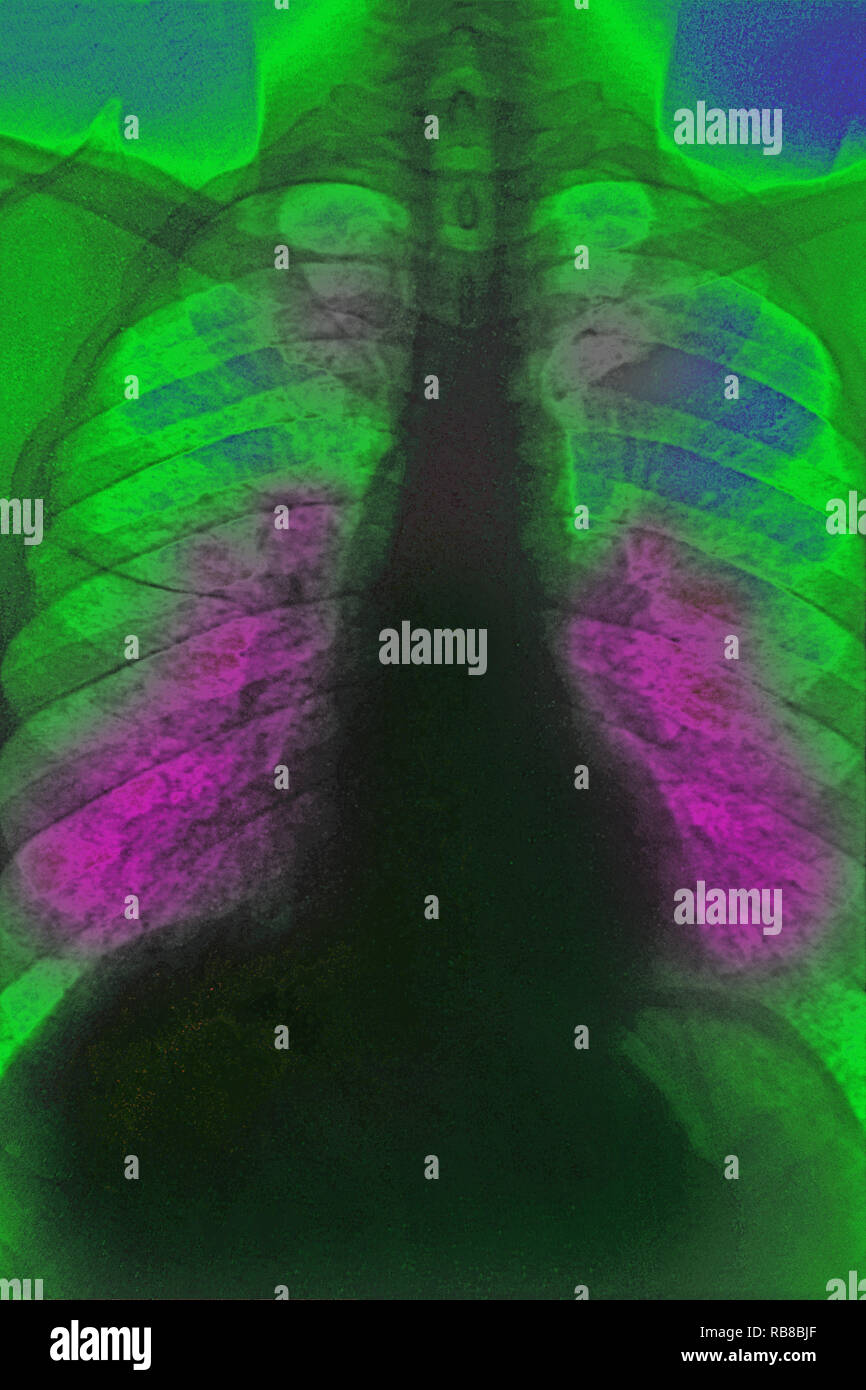

From www.alamy.com

Sarcoidosis. Frontal coloured chest Xray of the lungs of a 52yearold Sarcoidosis X Ray Images this review explores some of the key concepts in the imaging of pulmonary sarcoidosis: abnormalities may be seen on chest radiographs in more than 90% of patients with thoracic sarcoidosis. Pulmonary fibrotic changes may also. The radiograph may appear normal. sarcoidosis can involve all of the organ systems of the body, but thoracic lymph nodes and the. Sarcoidosis X Ray Images.